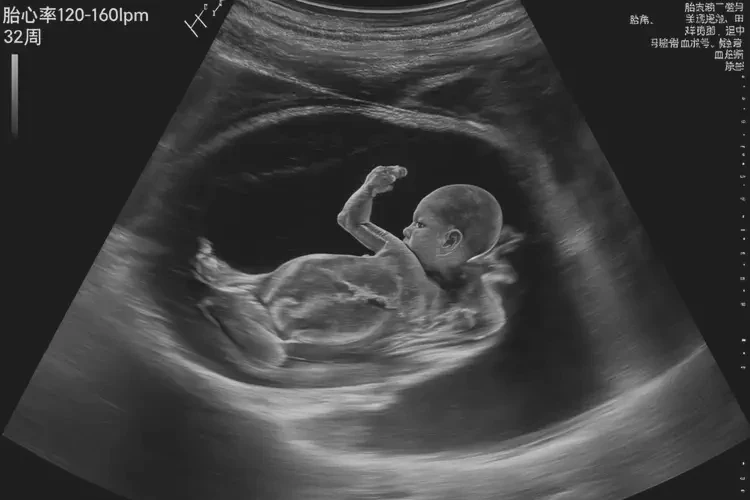

胎心106次/分钟在怀孕第32周不正常。

怀孕第32周时,胎儿的正常胎心率范围应在120-160次/分钟之间。胎心率低于120次/分钟或高于160次/分钟都可能表示胎儿存在健康问题,需要进一步检查和评估。

胎儿的心率在不同的孕周会有所变化。以下是胎儿心率的正常范围:孕周 正常心率范围(次/分钟) 12-16周 140-170 17-20周 130-160 21-24周 120-150 25-28周 110-140 29-32周 120-160 33-36周 110-150 37周以上 110-150 从上表可以看出,在怀孕第32周时,胎儿的正常心率范围应在120-160次/分钟之间。

胎心106次/分钟在怀孕第32周不正常,可能表示胎儿存在健康问题。孕妇应定期进行产检,包括胎心监测,及时发现并处理潜在的问题,以确保胎儿的健康发育。